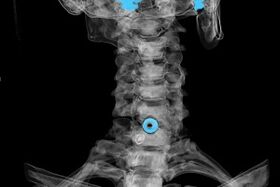

The diagnosis is made on the basis of characteristic symptoms, as well as using:

- X-rays.The method is ineffective, especially in the last stages of the development of osteochondrosis.

- MRI (magnetic resonance imaging) of the cervical spine.A method that allows you to see bone structures, herniated intervertebral discs, their size and direction of development.

- Computed tomography.A less effective solution than MRI, because the presence and size of the hernia is difficult to determine.